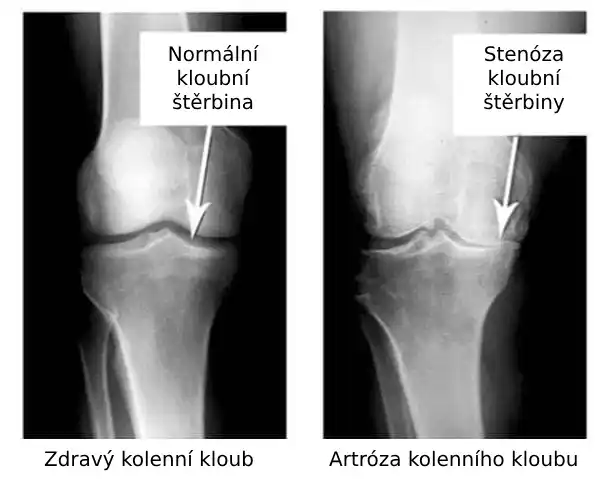

Podívejte se na tyto obrázky, můžete vidět, že na obrázku vpravo není žádný kloubní prostor, kosti se o sebe třou a způsobují silnou bolest. A tento proces je velmi těžké zastavit! Za pár let se ten člověk stane invalidním a už se nebude schopen sám živit.

Markéta Svobodová: Především jsou to vážná zranění a napětí. Nadváha také hodně zatěžuje vaše klouby. Sedavý způsob života, stres, nadbytek soli a cukru ve stravě, to vše změkčuje chrupavčitou tkáň, opotřebovává ji a ředí. Při každém novém pohybu se chrupavka ničí a deformuje a kosti se o sebe začnou třít, což způsobuje nesnesitelnou bolest.